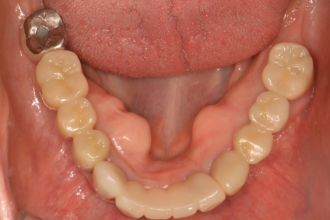

임플란트